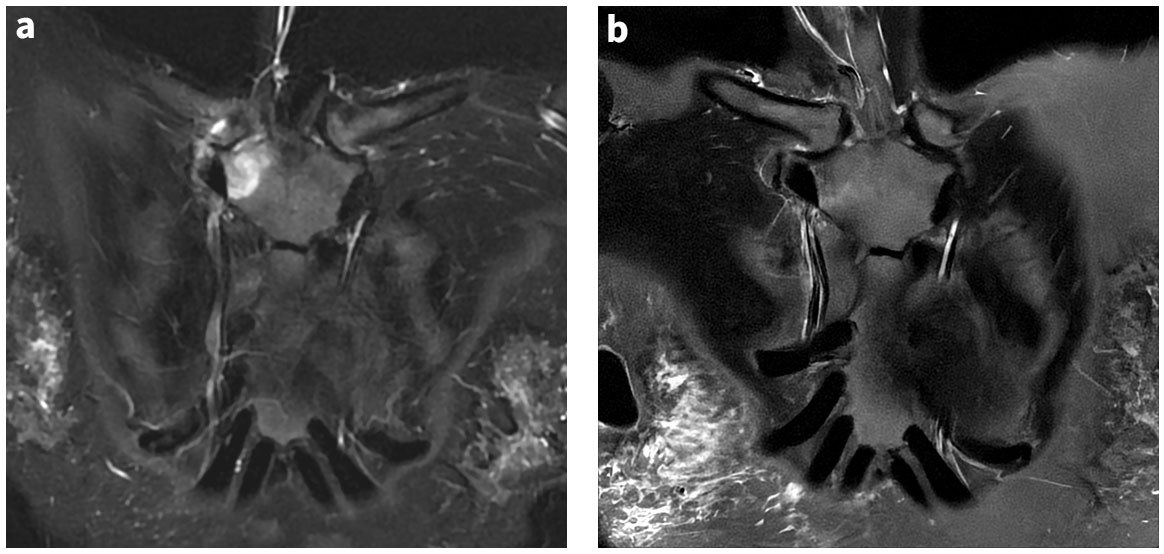

6. PROPELLERとAIR™ Recon DLのシナジー

第52回 日本磁気共鳴医学会大会にて, 肩関節撮像を想定した動態ファントムによるPROPELLER w/DLの体動補正効果について報告した. Fig.6aが動態ファントムである. Fig.6b左の画像は, 動態ファントムをCartesianで撮像したものであるが, 普段目にするモーションアーチファクトが再現されている. Fig.6b右の画像は動態ファントムをPROPELELR w/DLで撮像したものであるが, モーションアーチファクトの無い画像を取得できていることがわかる. Fig.6cにてプロファイルカーブを参照すると, 動態ファントムをPROPELELR w/DLで撮像した画像は, 静止ファントムを撮像した場合と同等のプロファイルカーブを示し, 良好な体動補正効果をもたらすことが示唆される.

Artist_Yokohamaminamikyousai08.jpgFig.6 肩関節想定動態ファントムを用いた PROPELLER w/DL の体動補正効果

(a) 肩関節想定動態ファントム

(b) 動態における Cartesianと Propeller w/DL 画像

(c) 静態/動態, DLの有無,Cartesian/Propellerの違いによるファントム(左側)のプロファイルカーブ